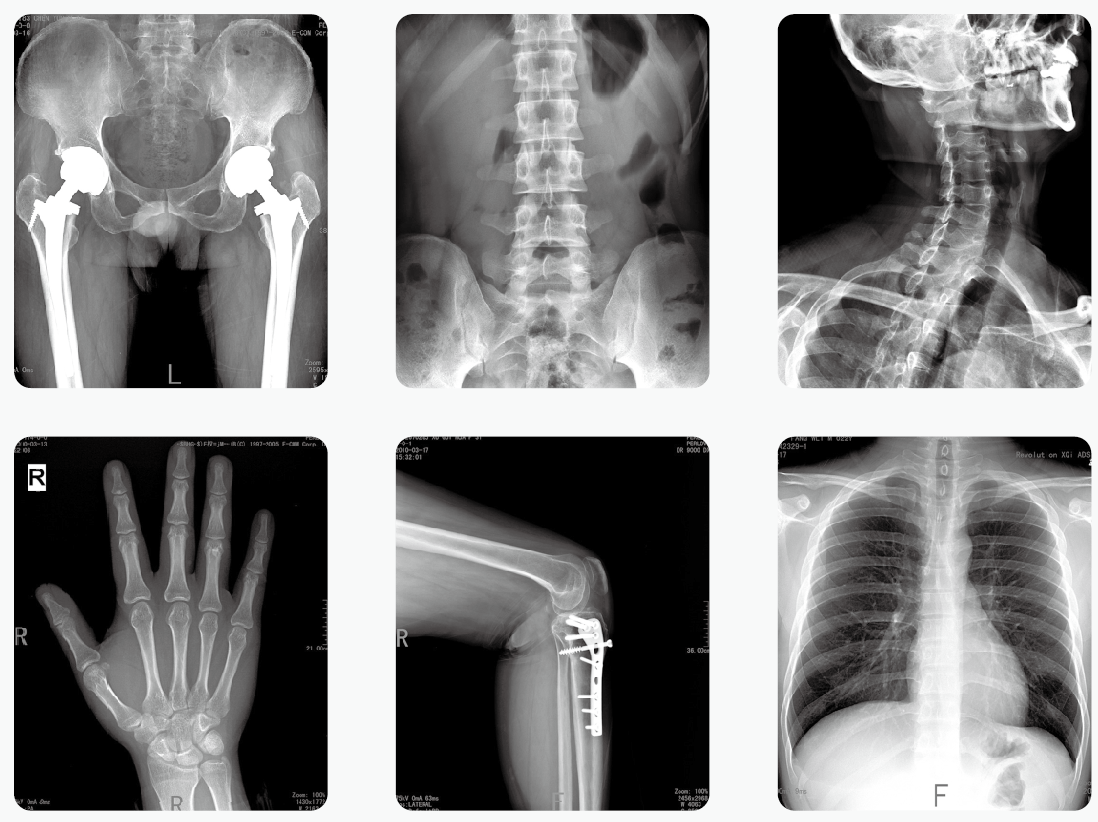

其实,绝大部分医用X光机检查的部位都是四肢、头、牙齿或者胸部,孕妇的生殖腺并没有直接暴露在X光下。因此,在这些情况下,只要合理曝光及防护,对胎儿是没有危害和影响的。

但是,如果孕妇需要做腹部、盆腔、腰椎等医用X光机检查,此时胎儿是直接暴露在X光下的,这种情况就需要与医生探讨X光检查的利弊后再做决定。